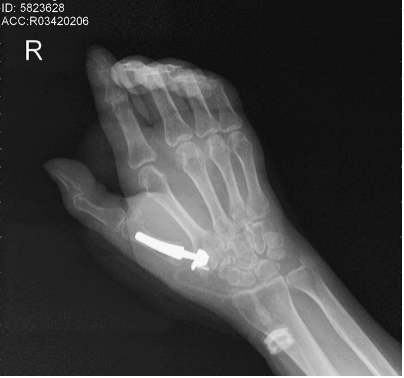

【智能装备网讯】       患者于阿姨(化名),多年来一直受到右手疼痛的困扰,就诊于多家医院均诊断为右手第一掌指关节炎,关节面受累明显,掌指关节半脱位,接受了包括口服药、敷药、注射等多种疗法都无明显效果,活动明显受限,而且关节疼痛难耐,生活质量受到严重影响。

△术前影像学检查提示右侧第一腕掌关节炎,腕掌关节半脱位。

△右手第一腕掌关节周围肿胀疼痛,活动明显受限。